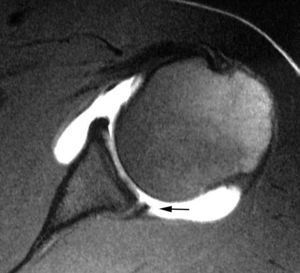

El TLB, LCH y el ligamento coracoacromial (LCA) son también estructuras importantes que contribuyen en diferentes formas a la biomecánica normal del hombro. El LCH ha recibido cierta atención en la literatura reciente y, hoy en día, es considerado una estructura importante junto con el LGHS en la estabilidad del TLB, las lesiones de pinzamiento anterosuperior y en las lesiones del intervalo del MR. La relación anatómica entre estas estructuras (TLB, LCH y el LGHS) es compleja. El punto de origen de cada una de estas estructuras es diferente, pero las tres confluyen en una zona situada, aproximadamente, en el borde superior del troquiter (fig. 6). El TLB se inserta en el borde superior del LG y en el tubérculo bicipital. El LCH se origina en la base de la coracoides y se inserta en el borde superior del troquier por encima y por delante del TLB. El LGHS se origina en el borde superoanterior del LG y se inserta en el borde superior del troquiter, por debajo del TLB.

Fig. 6.--Anatomía del ligamento coracohumeral (LCH), tendón largo del bíceps (TLB) y ligamento glenohumeral superior (LGHS) (polea reflectora). En un corte medial (1) el LCH se halla por encima del TLB y el LGHS por delante. En un corte intermedio (2) el LGHS se halla por delante del TLB. En un corte más lateral (3) el LGHS se encuentra por debajo del TLB.